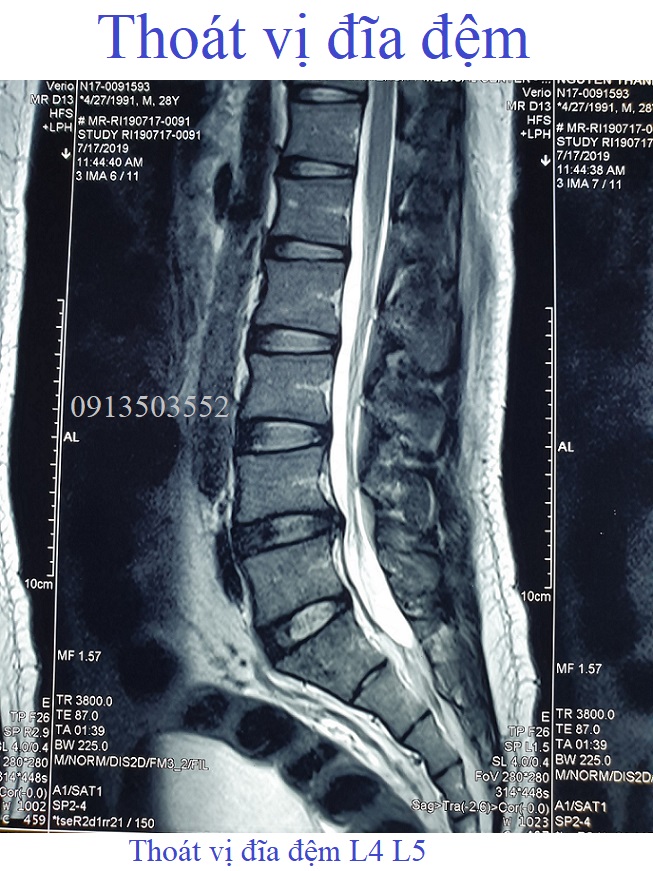

Thoát vị đĩa đệm L4 L5Thoát vị đĩa đệm L4 L5, kích thước 6mm, chèn ép vào rễ thần kinh L5 hai bên và gây hẹp ống sống (đường kính trước - sau #6mm)❮ đọc tiếp ❯